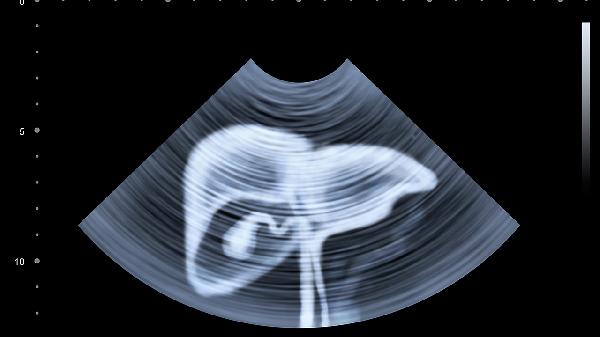

肝脏硬度检查报告单主要通过弹性成像技术评估肝纤维化程度,关键指标包括硬度值、参考范围及临床分级。

肝脏硬度检查通常采用瞬时弹性成像或剪切波弹性成像技术,检测结果以千帕为单位。正常肝脏硬度值一般在2.5-7.0千帕,超过7.0千帕提示可能存在肝纤维化。7.0-9.5千帕对应轻度纤维化,9.5-12.5千帕提示中度纤维化,12.5-14.5千帕属于显著纤维化,超过14.5千帕需警惕肝硬化可能。报告单会标注具体测量值及对应分级,部分设备会显示10次有效测量的中位数及四分位间距,四分位间距与中位数比值小于30%说明数据可靠性较高。检查结果需结合血清学指标如APRI、FIB-4指数及影像学检查综合判断,肥胖、肋间隙狭窄、急性肝炎发作期可能影响检测准确性。